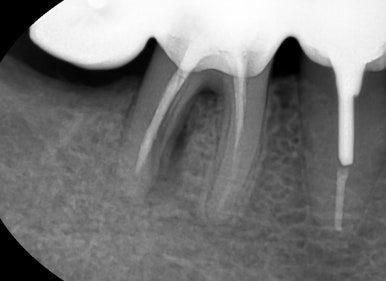

치아 뿌리가 가로로 파절된 선이 보입니다

치아뿌리가 가로로 파절된 선이 보입니다

보이시나요?

표시해드릴게요 ↓